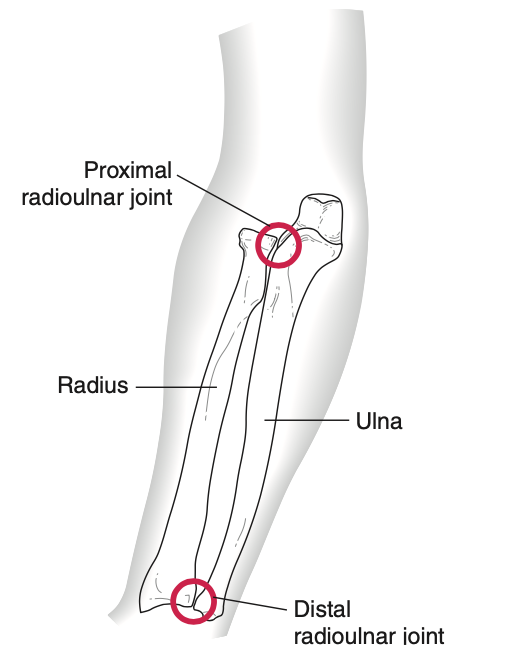

Khớp cẳng tay: quay -trụ (gần –xa)

Là khớp xoay (pivot)

- Đầu gần xương quay xoay quanh đầu gần xương trụ

- Đầu xa xương quay xoay quanh đầu xa xương trụ

- Dây chằng vòng giữ đầu xương quay trong khớp của nó

- Màng gian cốt tạo khớp nối giữa xương quay và xương trụ giữ hai khớp quay trụ gần và xa